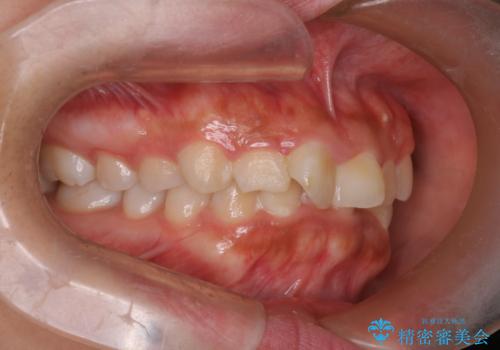

目立たない矯正で中等度の叢生を改善

- 歯のデコボコ(叢生)を気にされて来院されました。精密な検査の結果、中等度の叢生と診断。患者様のご希望に合わせ、透明で目立ちにくい**インビザライン(マウスピース矯正)**による治療計画を立案しました。歯を抜かずに、歯列弓(歯が並ぶアーチ)を少しずつ拡大することで、歯が並ぶスペースを確保し、叢生を改善することを目指します。

今回の矯正治療では、透明なマウスピース型の装置インビザラインを使用しました。この装置は目立ちにくく、取り外しが可能なため、食事や歯磨きも普段通りに行えます。治療は、緻密に計算された治療計画に基づき、段階的に作製されたマウスピースを交換していくことで、歯列弓全体を徐々に広げていきました。この歯列弓の拡大により、不足していたスペースを確保し、歯のデコボコを効果的に解消。抜歯することなく、整った美しい歯並びと良好な咬み合わせを獲得していただけました。